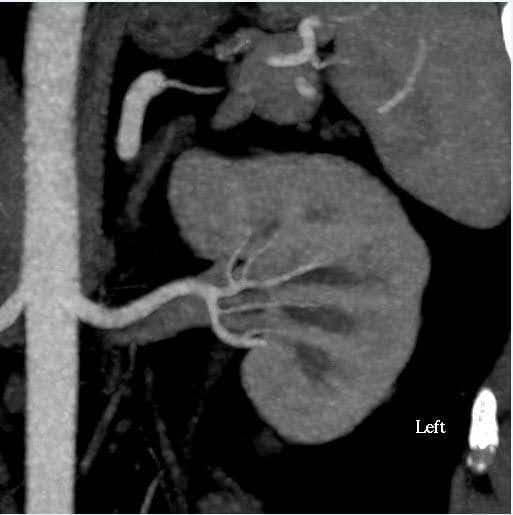

Böbreklerin büyüklüğünün yanı sıra böbrek damar sistemi ve toplayıcı sistemdeki anatomik varyasyonları değerlendirmek için karın BT anjiyografisi yapıldı (Şekil 1). Bu durumda, böbreklerin tahmini hacmi% 10'dan daha az bir tutarsızlığa sahipti, bu da fonksiyonel test merkezimiz için son sınırdır. Donörde bilateral tek renal arter ve tek renal ven vardı. Renal pelvis veya üreterlerde herhangi bir anormallik kaydedilmedi. Sol böbreğin üst polünde 2 cm'lik basit benign görünümlü kortikal kist görüldü. Böbreklerde taş veya anormal kitle saptanmadı.

Şekil 1. BT anjiyografi karın (böbrek). Sol: sol tarafta tek renal arter ve veni gösteren eksenel görünüm; Sağ: koronal görünüm Sol böbrek.